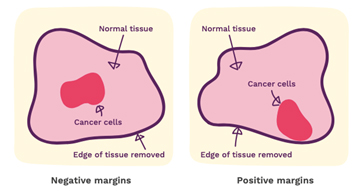

Understanding Surgical Margins In Breast Cancer

www.verywellhealth.com

cancer margins surgical margin affect understanding ferster verywell

margin conserving surgery breast cancer clear figure

Guide To Understanding Surgical Margins | KUBTEC

breast cancer margins guidelines surgery safe newsmax multiplies plastics chemical blood test outdoor night light set cells increases risk compound

evidence margins surgery breast cancer such clear why good